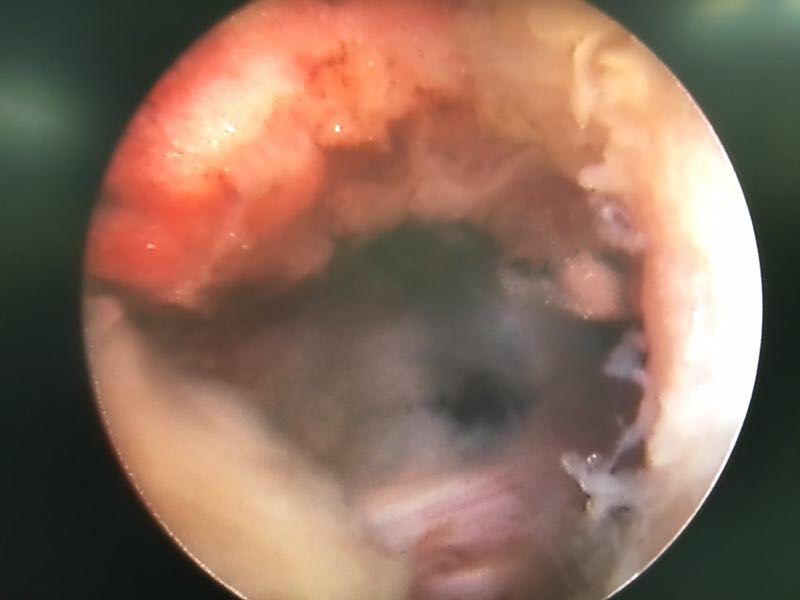

椎间孔镜下腰5骶1椎板间隙入路髓核摘除术

诊断:腰5骶1椎间盘突出症 治疗方案:椎间孔镜下经椎板间入路髓核摘除术